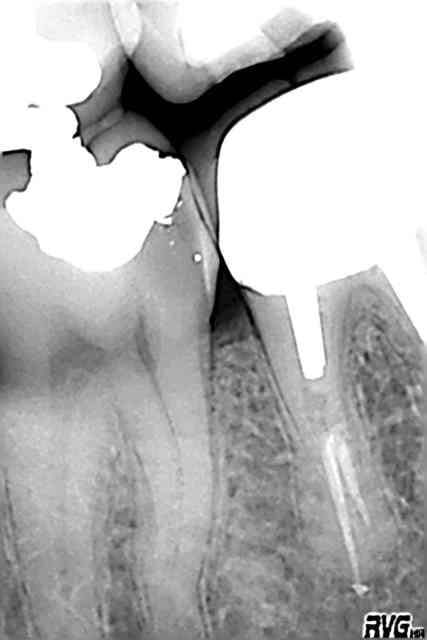

y a bien une résorption interne. pj la préop

Annie, je me trompe peut-être mais je crois que la 13 a un max de canaux accessoires en mésial. t'as pas la préop al ?

oui effectivement la 13 a plein de petits canaux accessoires,ils étaient cachés par le petit encart d'impression